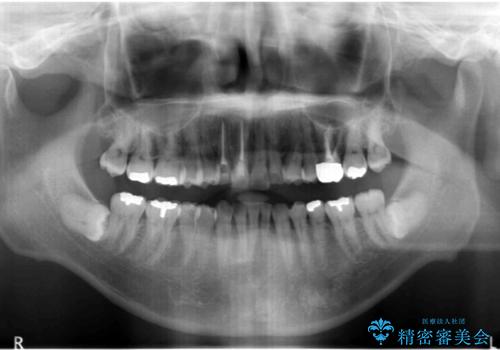

患者様の「できるだけ短期間で治療を終わらせたい、セラミックが入れられたら良いので大がかりなことはしたくない」とのご要望により、3Dシミュレーションを何度も行い患者様とのコンサルを重ね、上顎左右犬歯と左下2を抜歯して②のプランである補綴前矯正(インビザライン)を行うことにしました。

小臼歯の歯根長が長いことを治療前にレントゲンで確認し抜歯部位を決定しました。